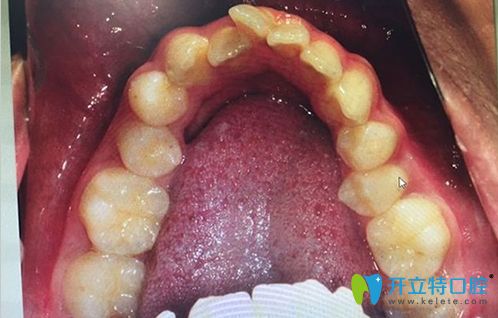

擴弓矯正的前后效果對比圖